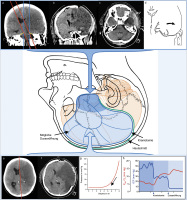

Hemikraniektomie

Abbildung 1: Die der dekompressiven Hemikraniektomie bei malignem Mediainfarkt zugrundeliegenden pathophysiologischen Überlegungen und wesentliche chirurgischtechnische Aspekte sind schematisch zusammengefasst. In fortgeschrittenen Stadien des raumfordernden Mediainfarkts tragen 2 Faktoren wesentlich zur lebensbedrohlichen klinisch-neurologischen Verschlechterung bei: (1) Dekompensation der intrakraniellen Druck-Volumenbeziehung mit globaler Hirndrucksteigerung und kritischer Reduktion des zerebralen Perfusionsdrucks. (2) Axiale Hirnstammkompression durch ischämische Schwellung des supratentoriellen Parenchyms, in späteren Stadien transtentorielle Herniation temporomesialer Parenchymbezirke. Die Ziele der dekompressiven Hemikraniektomie sind (1) adäquate Hirndrucksenkung durch großflächige Dekompression der Hemisphäre und (2) suffiziente axiale Hirnstammdekompression durch temporale knöcherne und durale Entlastung. Durch die fokal raumfordernde Wirkung des ischämisch geschwollenen Infarktareals kommt es zu Parenchymshifts, die zu axialer Hirnstammkompression und in fortgeschrittenen Stadien zur Herniation führen können. Durch rechtzeitige suffiziente knöcherne und durale temporobasale Entlastung ist eine axiale Dekompression des verlagerten Hirnstamms (a, b) und Rückbildung der temporomesialen Herniationszeichen (c, d) zu erreichen. Bei einem raumfordernden Territorialinfarkt der Arteria cerebri media mit globaler Hirndrucksteigerung und deutlicher Mittellinienverlagerung (e) kann durch großflächige Entlastungskraniotomie eine suffiziente Dekompression der Hemisphäre mit deutlicher Senkung des intrakraniellen Drucks und Rückbildung der Mittellinienverlagerung erzielt werden (f). Vor dem Hintergrund der exponentiellen intrakraniellen Druck-Volumenbeziehung ist eine rasche Dekompensation im Vorfeld der Operation möglich, andererseits eine ebenso rasche Rekompensation nach zeitgerechter Entlastungskraniotomie (g). Die wesentliche Hirndrucksenkung und Steigerung der zerebralen Gewebsoxygenierung findet erst nach Eröffnung der Dura statt (h).